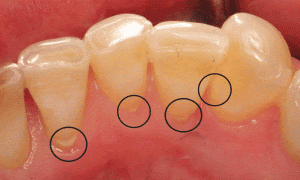

Ngoài ra, sự tích tụ của chất bám và vi khuẩn trên bề mặt răng cũng là một trong những yếu tố gây ra tình trạng này. Vi khuẩn trong miệng của chúng ta sẽ tiếp xúc với thực phẩm và nước bọt, tạo thành một lớp chất bám dính trên bề mặt răng. Nếu không được vệ sinh đúng cách, lớp chất bám này sẽ dần dần tích tụ và trở nên khó loại bỏ, gây ra sự kết hợp với khoáng chất và tạo thành cao răng.

Một trong những tác hại đáng chú ý nhất của cao răng là khó khăn trong việc vệ sinh răng miệng. Các mảng bám thức ăn tích tụ và vôi hóa tại mép lợi và sát giữa các kẽ răng sẽ khiến cho chúng ta gặp khó khăn khi vệ sinh răng miệng. Bất kể chúng ta dùng tăm chỉ hay chỉ nha khoa, đều sẽ đều bị cản trở và không lấy hết được các mảnh vụn trong các kẽ răng. Nếu để tình trạng này diễn ra lâu dài, cao răng sẽ ngày càng tăng lên, dẫn đến sự hình thành của sâu răng và các vấn đề khác cho sức khỏe răng miệng.

Ngoài ra, cao răng còn gây ra tác hại về mặt thẩm mỹ. Khi được tích tụ dần dần, từng lớp và ngày một dày lên, lượng cao dày bám ở mép lợi, với màu trắng đục hoặc vàng sẽ gây mất thẩm mỹ cho răng miệng của bạn. Khi đó, bạn dễ dàng cảm thấy tự ti khi tiếp xúc với người khác và không được thoải mái. Hơn nữa, cao răng cũng có thể gây ra tình trạng hôi miệng. Cao răng tích tụ tại răng bị vôi hóa sẽ tạo ra mùi hôi khó chịu. Nếu tình trạng nặng và kéo dài, nó sẽ khiến cho chúng ta luôn cảm thấy e ngại khi nói chuyện với người khác.